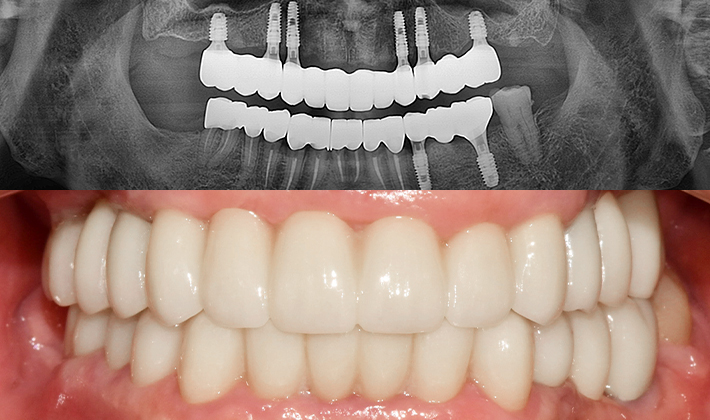

실제 치료 사례

수많은 환자들이 고민 끝에 선택한 치료,

그리고 그 후의 놀라운 변화

- ※ 위 임상사진은 365서울원탑치과에서 진료를 시작하고 마친 동일한 환자의 사진입니다.

- ※ 위 임상사진은 동일한 장소에서 동일한 조건으로 촬영되었으며, 사진에 대한 별도의 조작이 처리되지 않았습니다.

- ※ 수술 및 치료 과정에서 부작용이 발생할 수 있으므로 의료진과의 충분한 상담과 신중한 판단이 요구됩니다.

환자를 향한 진심,

완성도 높은 결과

환자의 상태를 세심하게 살피고,

글로벌 스탠다드에

맞춘

진단과

치료 과정을 통해 보다 안전하고

완성도

높은 결과를 만듭니다.